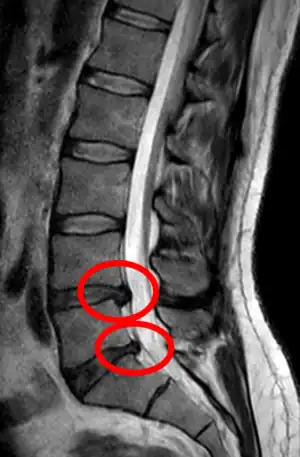

Click images to see larger versions

• Magnetic resonance imaging is the gold standard study for confirming a suspected LDH. With a diagnostic accuracy of 97%, it is the most sensitive study to visualize a herniated disc due to its significant ability in soft tissue visualization. MRI also has higher inter-observer reliability than other imaging modalities. It suggests disc herniation when it shows an increased T2-weighted signal at the posterior 10% of the disc. Degenerative disc diseases have shown a correlation with Modic type 1 changes. When evaluating for postoperative lumbar radiculopathies, the recommendation is that the MRI is performed with contrast unless otherwise contraindicated. MRI is more effective than CT in distinguishing inflammatory, malignant, or inflammatory etiologies of LDH. It is indicated relatively early in the course of evaluation (<8 weeks) when the patient presents with relative indications like significant pain, neurological motor deficits, and cauda equina syndrome. Diffusion tensor imaging is a type of MRI sequence used for detecting microstructural changes in the nerve root. It may be beneficial in understanding the changes that occur after herniated lumbar disc compresses a nerve root, and might help in differentiating the patients that need surgical intervention. In patients with a high suspicion of radiculopathy due to lumbar disc herniation, yet the MRI is equivocal or negative, nerve conduction studies are indicated.[44] T2-weighted images allow for clear visualization of protruded disc material in the spinal canal.